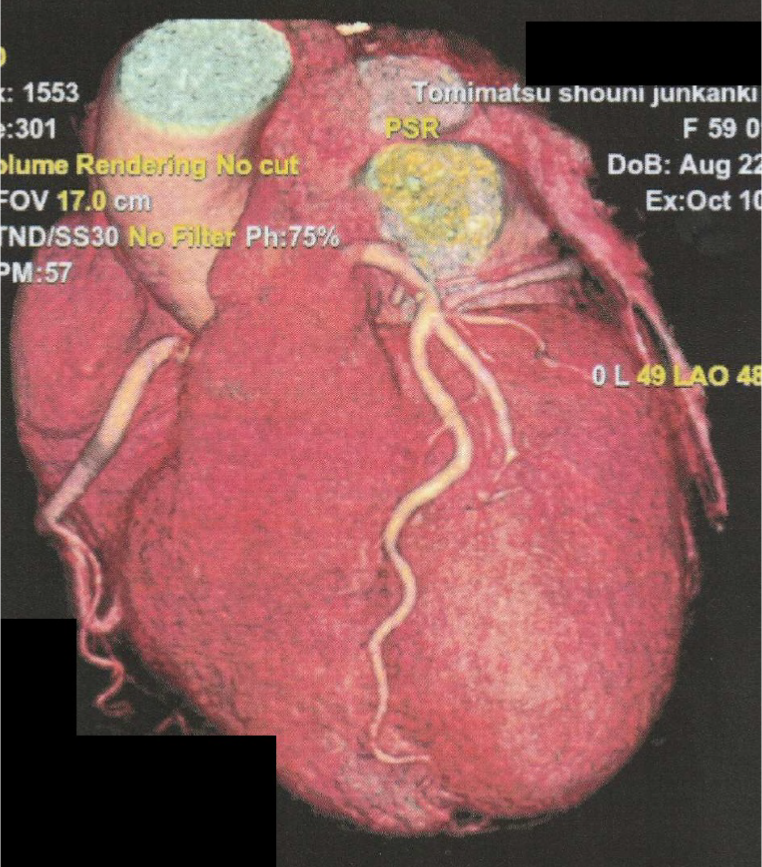

・心臓造影CT

冠動脈の狭窄や心機能などを評価します。